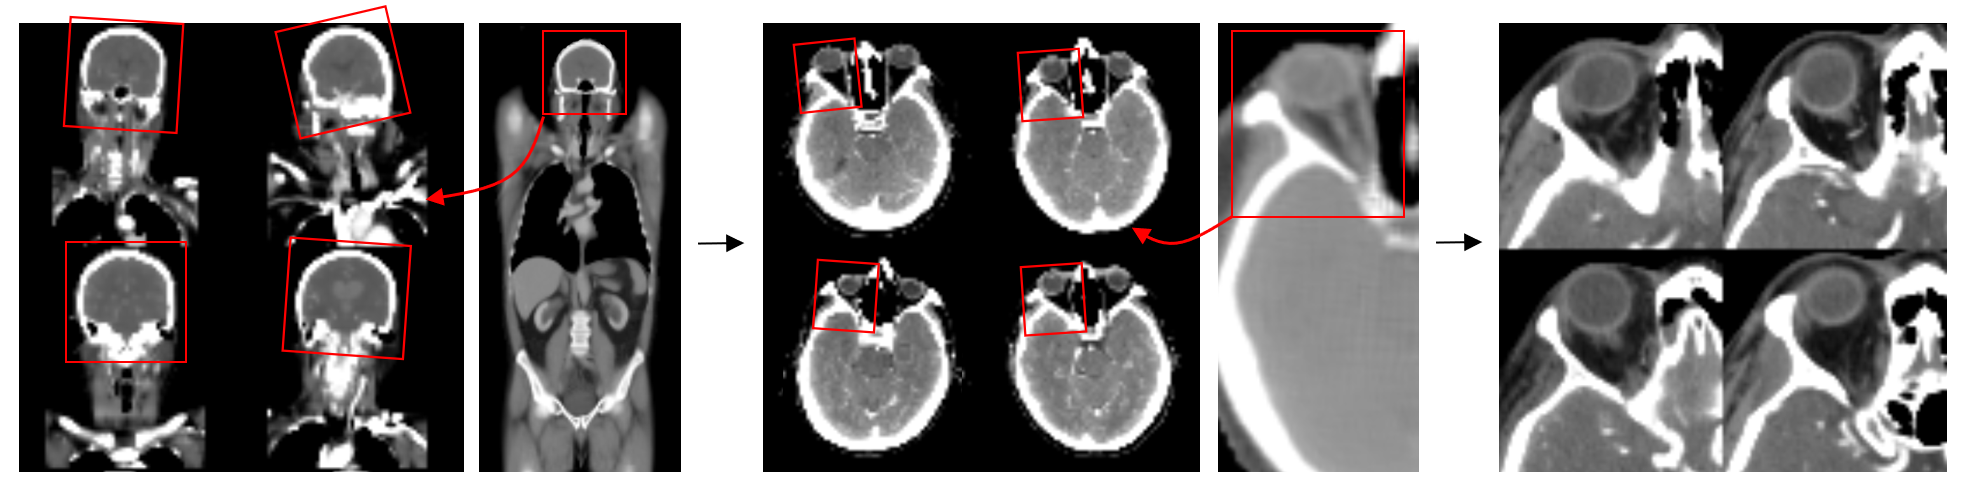

The self-supervised DeepATLAS framework yields a flexible, generalized representation of anatomic structure with the capacity for one-shot or few-shot localization on high-dimensional biomedical data. While supervised models for localizing anatomy have become increasingly prevalent and comprehensive in recent years [3, 32, 33], there is inevitably a need to solve for new tasks not already addressed by existing algorithms. In this context, the proposed DeepATLAS strategy is a much more efficient and scalable alternative, with reasonable one-shot generalizability for most problems. In addition, conventional segmentation or bounding box models provide only coarse estimates of structure compared to granular DeepATLAS predictions, which in turn support more precise anatomic characterization such as orientation or internal structure. For example, instead of simply identifying the bounds of an anatomic target, DeepATLAS may further reorient the region of interest into a standardized, consistent projection (Figure 8). Moreover, compared to recent zero-shot interactive segmentation algorithms [10, 11], DeepATLAS does not require identifying seed regions or initial predictions on an exam-by-exam basis. Finally, as a domain-agnostic unsupervised paradigm, the proposed methods may be easily extended to various other biomedical datasets.